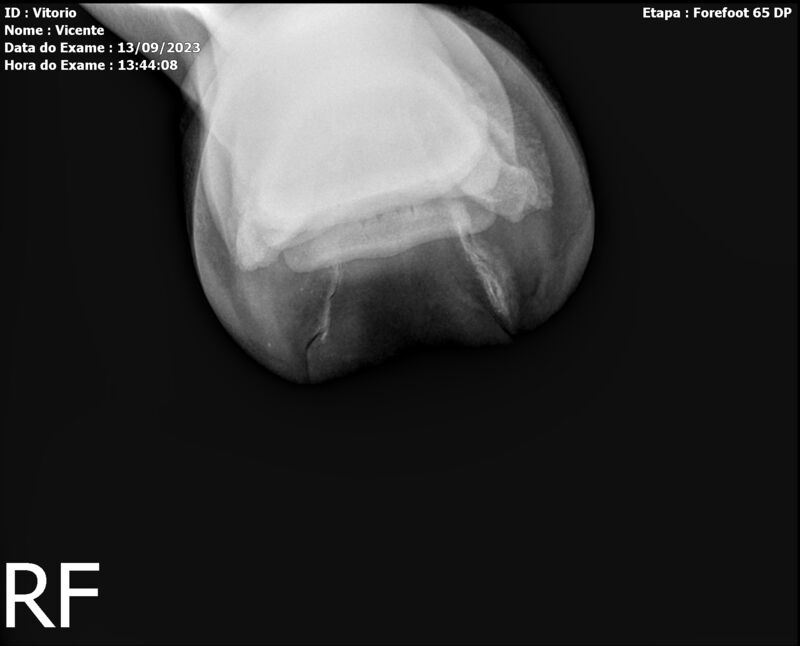

LOTE 13

THUNDER ZC

Raça: BRASILEIRO DE HIPISMO

Sexo: MACHO - POTRO

Nascimento: 17/09/2022

Altura Aproximada: 1,54

Pel.: CASTANHO

Registro: EM AND

Vend.: VICENTE CONTE

Local : PORTO FELIZ/SP